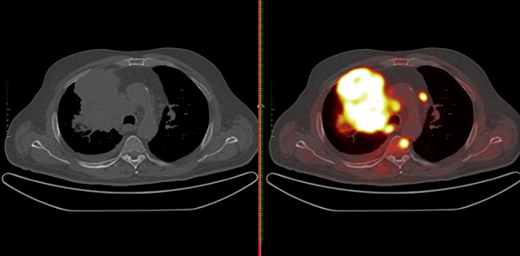

Позитронно-эмиссионная томография в комбинации с компьютерной томографией, или ПЭТ/КТ — наиболее предпочтительный диагностический метод, который используется для стадирования рака легкого. Для его проведения применяется специальное контрастное вещество — 18F-фтордезоксиглюкоза. ПЭТ/КТ позволяет наглядно увидеть опухоль в легком, отдаленные метастазы, а также понять, вовлечены ли в опухолевый процесс регионарные лимфатические узлы. При изучении снимков ПЭТ/КТ онкологи обращают особое внимание на медиастинальные, или средостенные лимфоузлы, расположенные в грудной клетке. Их поражение существенно меняет дальнейший план и объем лечения. Пораженные лимфоузлы накапливают контрастное вещество сильнее, чем здоровые ткани, что вызывает сильное свечение на снимке.

Свечение опухоли на ПЭТ/КТ